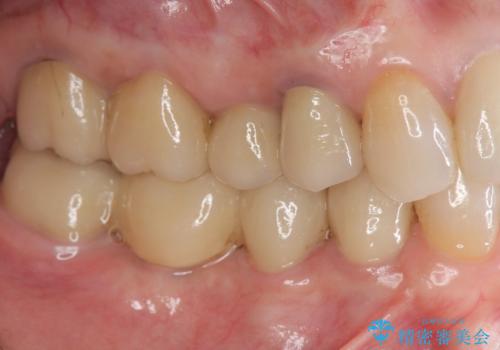

臼歯部メタルフリー再補綴

![[ インプラント治療 ]失った奥歯を回復したいの症例 治療後](https://seimitsushinbi.jp/wp/wp-content/uploads/2021/11/7d51b0ec04f819febabdd26c9bfb7954-500x350.jpg?v=1637928867)